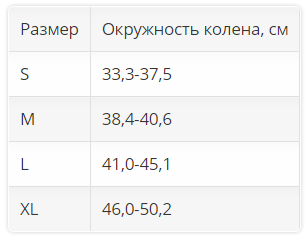

Размер. Для определения размера нужно измерить окружность колена.

| Размер | Окружность колена, см |

| S | 33,3-37,5 |

| M | 38,4-40,6 |

| L | 41,0-45,1 |

| XL | 46,0-50,2 |